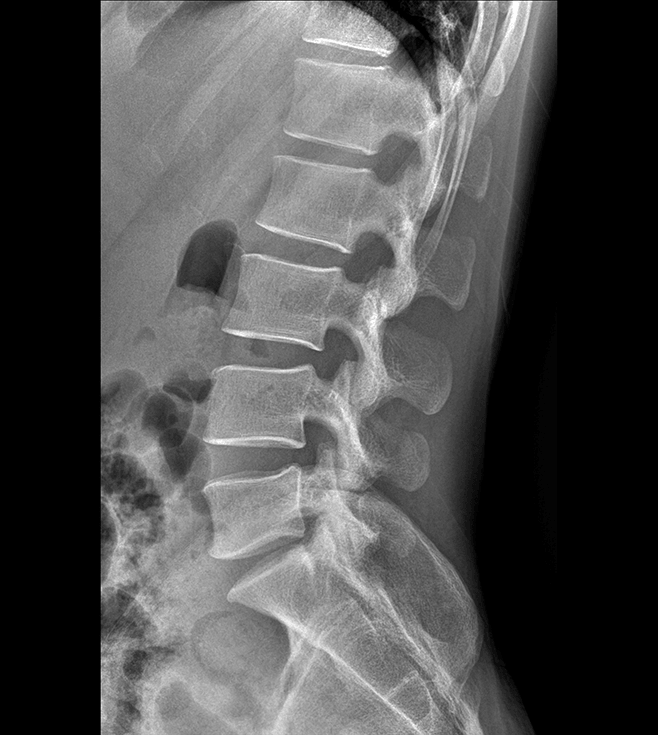

多功能诊断专用动态DR

太阳成集团tyc122cc入口科技全新设计的第四代床式动态DR,集拍片、透视、造影、全身拼接、尘肺体检于一体,一机多能,真正意义上实现全科室应用,提升医院实际效益。

高清动态平板探测器

搭载自主研发超清大视野动态平板探测器,600微米碘化铯大幅提升X线转化效率,独特的非晶硅阵列与高速读取集成电路紧密协作,轻松实现多帧率透视与高清点片。

专业的影像处理系统

“腾灵”系列搭载的IEAE影像处理系统,具备多项发明专利。本系统采用多频域图像处理技术,其6大核心处理模块使影像具有优秀的一致性、柔和性、空间层次感和纹理细腻度,为用户精准诊断病灶奠定了坚实的基础。